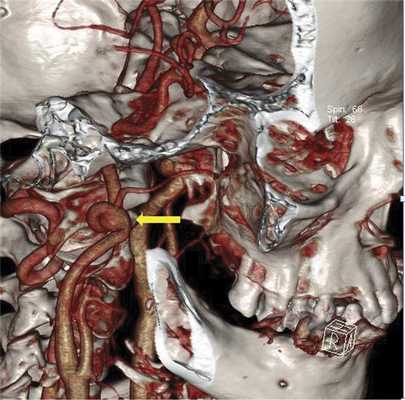

Пример аневризмы внутренней сонной артерии верхушки пирамиды височной кости

ФГБУ «Федеральный центр нейрохирургии» Минздрава России, Новосибирск, Россия

Оперативное лечение дистальных аневризм экстракраниального отдела внутренней сонной артерии, сочетающихся с ее патологической извитостью

Аневризмы экстракраниального отдела внутренней сонной артерии (ВСА), расположенные у входа в череп, являются редкой патологией. При данной патологии показано проведение хирургического вмешательства из-за опасности артерио-артериальной эмболии с развитием нарушения мозгового кровообращения. В отечественной и зарубежной литературе представлены единичные случаи или небольшие по числу наблюдений группы успешного хирургического лечения пациентов с дистально расположенными аневризмами внутренней сонной артерии в сочетании с ее патологической извитостью. Открытое оперативное вмешательство при этой локализации аневризмы является сложным из-за травматичности доступа. Проведение эндоваскулярных вмешательств не всегда возможно из-за наличия дегенеративных изменений сосудистой стенки и патологической извитости артерии. Предложен вариант хирургического вмешательства по созданию экстраанатомического высокопотокового шунта между наружной сонной артерией и М2 сегментом среднемозговой артерии. Представлены результаты успешного применения данной методики у 3 пациентов с дистально расположенными аневризмами экстракраниального отдела внутренней сонной артерии в сочетании с ее патологической извитостью.

В 2015 г. в отделении сосудистой нейрохирургии ФГБУ ФЦН Новосибирска выполнены 3 оперативных вмешательства у больных с диагнозом «Патологическая извитость ВСА с формированием мешотчатой аневризмы дистального отдела С1 сегмента». Все больные были в возрасте 62-63 года. Все они в анамнезе имели указание на нарушение мозгового кровообращения в бассейне СМА на стороне поражения ВСА: в 2 случаях - ишемический инсульт, в 1 - неоднократные ТИА. Больным была выполнена костно-пластическая краниотомия, создание высокопотокового экстраанатомического шунта между НСА и М2 сегментом СМА, проксимальное лигирование С1 сегмента ВСА.

При принятии решения о выборе метода хирургического вмешательства помимо общеклинических обследований учитывались данные дуплексного сканирования брахицефальных артерий (ДС БЦА), транскраниальной допплерографии (ТКДГ), мультиспиральной компьютерной томографической ангиографии (МСКТ-ангиографии) и магнитно-резонансной томографии (МРТ) головного мозга. По результатам ДС БЦА у всех пациентов выявлено нарушение хода ВСА в виде патологической извитости различной формы с ЛСК от 150 до 230 см/с. Аневризматическое расширение по данным УЗИ выявлено только в 1 случае. Более полная информация была получена по данным МСКТ-ангиографии экстра- и интракраниальных артерий, при которой во всех случаях выявлена патологическая извитость дистального отдела ВСА различной степени выраженности. В 2 случаях на уровне атланто-аксиального сочленения определялись мешотчатые аневризмы размером 8 и 12 мм, с частичным тромбированием аневризматического мешка (рис. 1). В 1 наблюдении выше аневризмы определялся участок надрыва интимы с фузиформным расширением дистального отдела ВСА.

Рис. 1. МСКТ-3D ангиография БЦА. Стрелкой указана дистально расположенная аневризма ВСА в сочетании с патологической извитостью артерии.